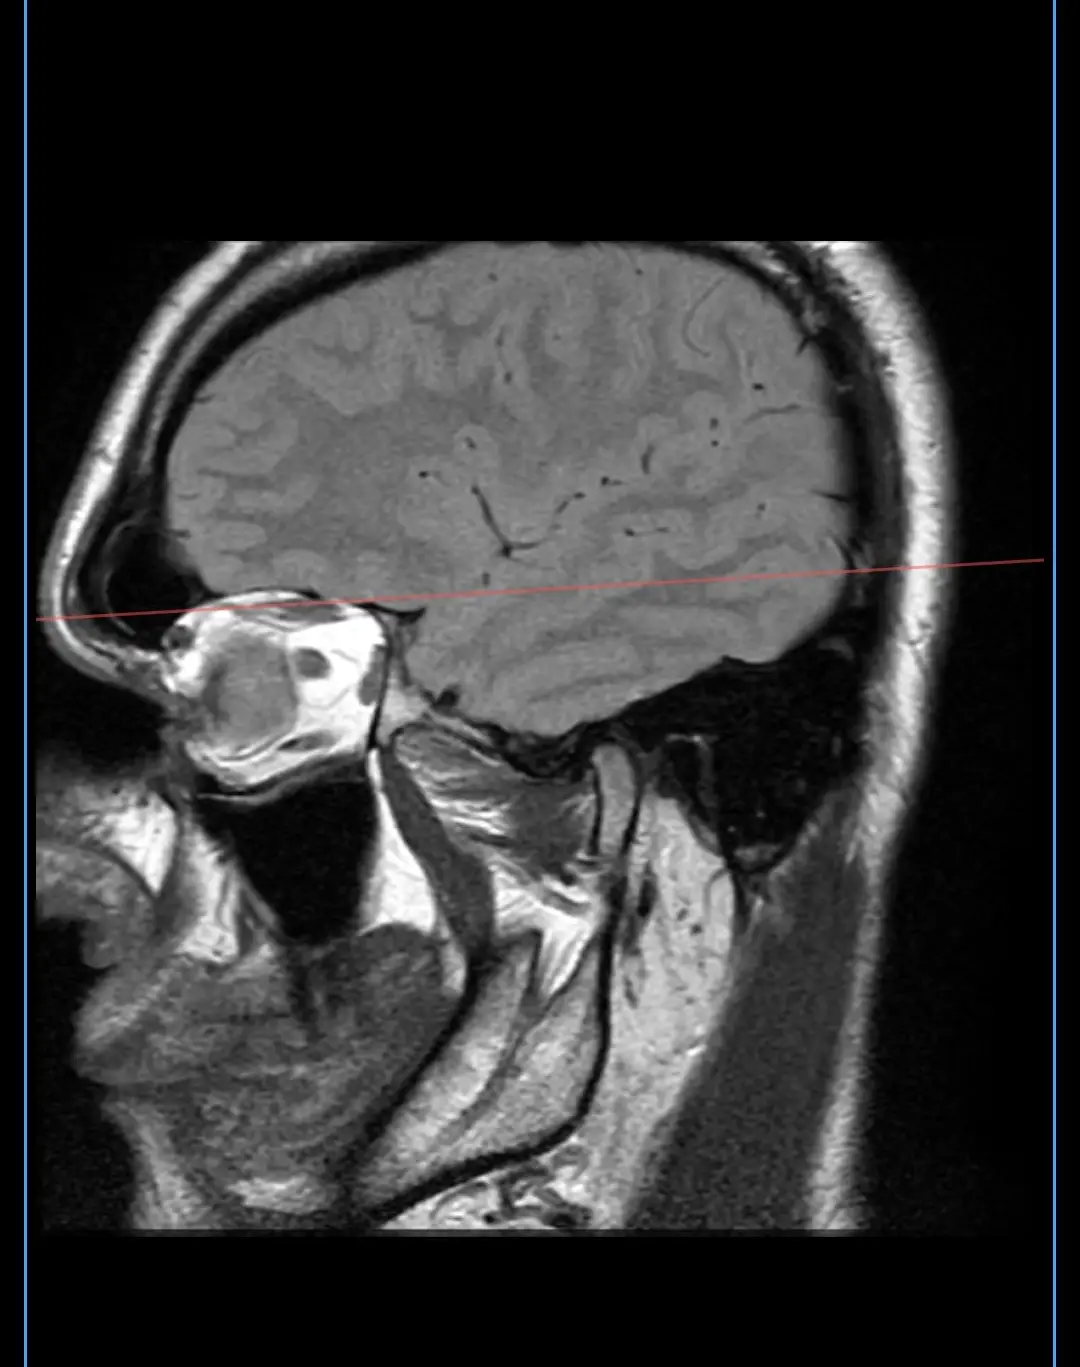

МРТ височно-нижнечелюстного сустава

Визуализация височно-нижнечелюстных сочленений (элементы сустава и суставной диск).